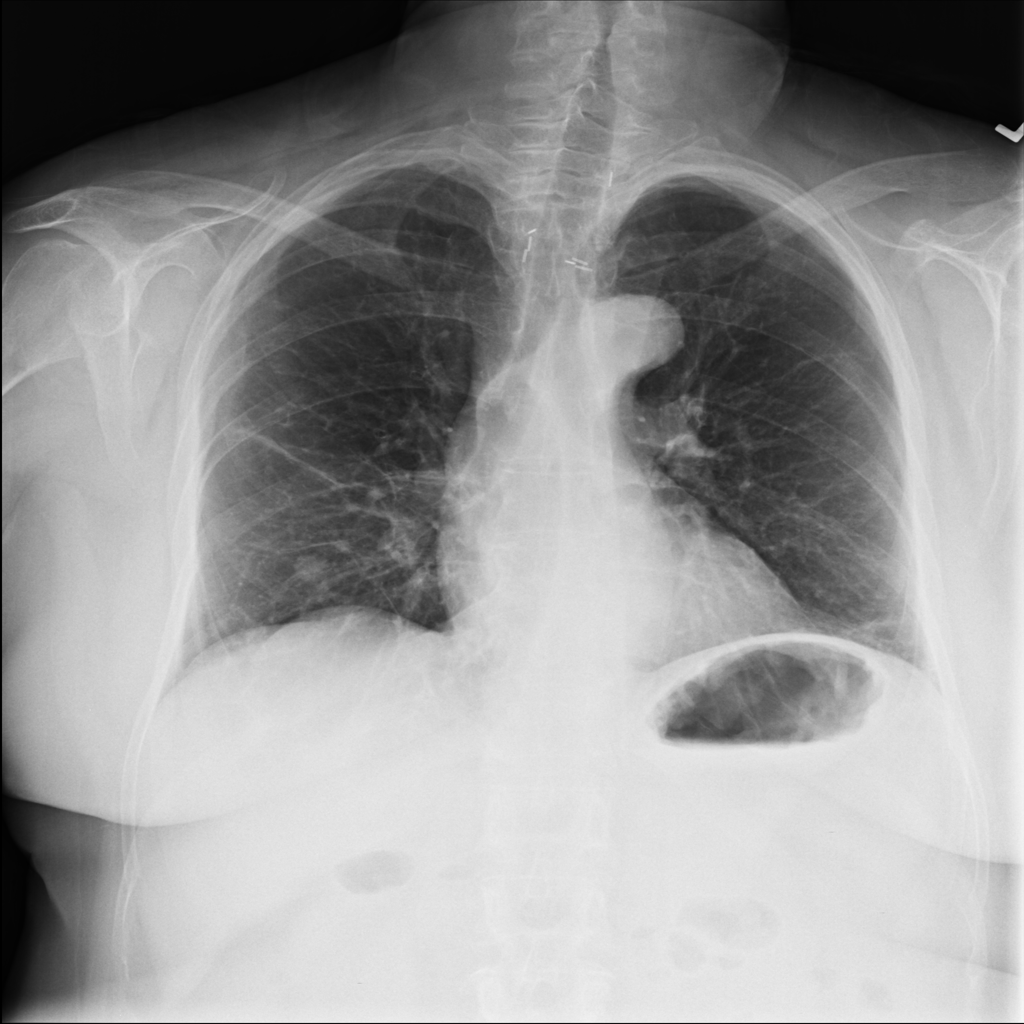

Nodule

A nodule is a small rounded opacity in the lung or chest field. It is a descriptive imaging finding that can be benign or more concerning depending on size, appearance, and context.

Showing up to 90 reference images for Nodule.